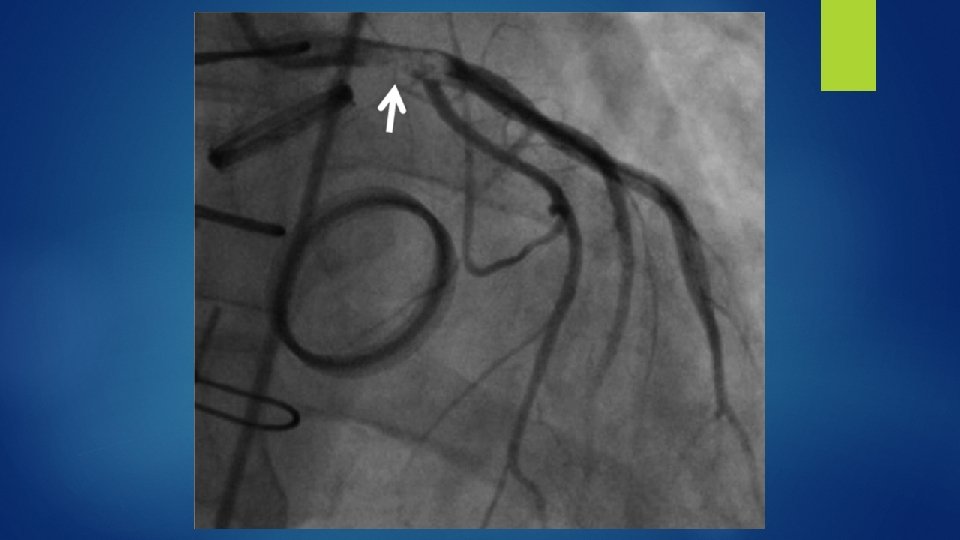

Patient had a severe ostial LAD thrombus that was close to the left main.